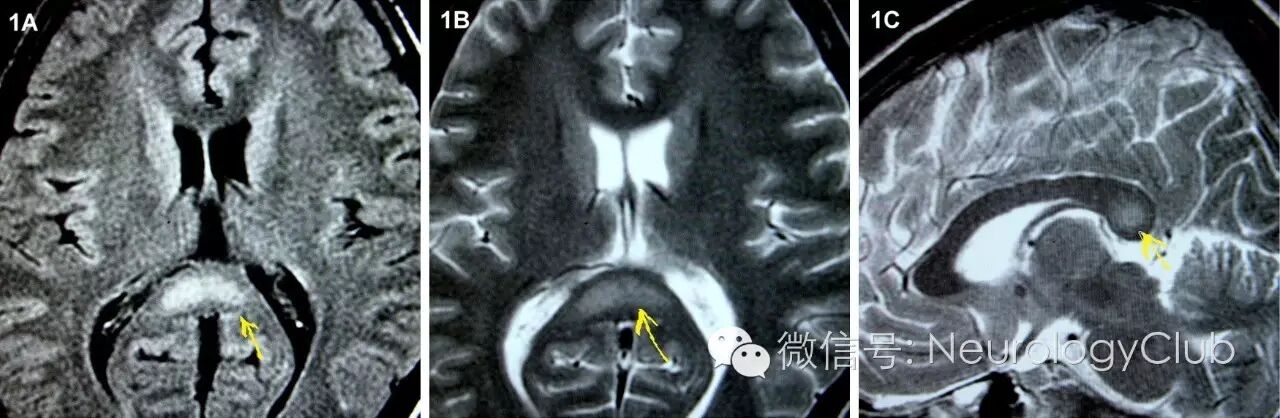

(图1:抗VGKC抗体相关的RESLES。起病7天后MRI上可见SCC病灶,22天后病灶消失。A与C:DWI;B与D:ADC

磁共振是诊断RESLES的首选检查。其特征性的影像学表现为SCC(一般位于中心区域)局限性的椭圆形或条状的病变,如出现整个胼胝体压部受累的条状病变,称为“回旋镖征”(Boomerang sign)。病灶于T1WI上呈等或低信号,T2WI/FLAIR和DWI上均为高信号,ADC值降低,增强扫描无明显强化。目前尚无胼胝体压部发生囊病或坏死的报道。病变可不仅仅局限在胼胝体压部,其他部位如膝部、体部也可同时出现,甚至可以累及胼胝体外,如脑室旁白质,皮质下白质和基底节区,而这些病灶基本上也是可逆的。最近的研究表明,胼胝体外病变的出现往往提示预后不良,而胼胝体其他部位是否出现病灶与预后并无明显联系。各种病因导致的RESLES影像学异常和消失的时间如表1所示。